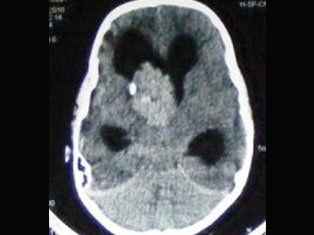

Brain Tumors

A brain tumor is a mass or growth of abnormal cells in your brain. Many different types of brain tumors exist. Some brain tumors are noncancerous (benign), and some brain tumors are cancerous (malignant).

Cerebro Vascular

A stroke occurs when the blood supply to part of your brain is interrupted or reduced, preventing brain tissue from getting oxygen and nutrients. Brain cells begin to die in minutes. A stroke is a medical emergency.